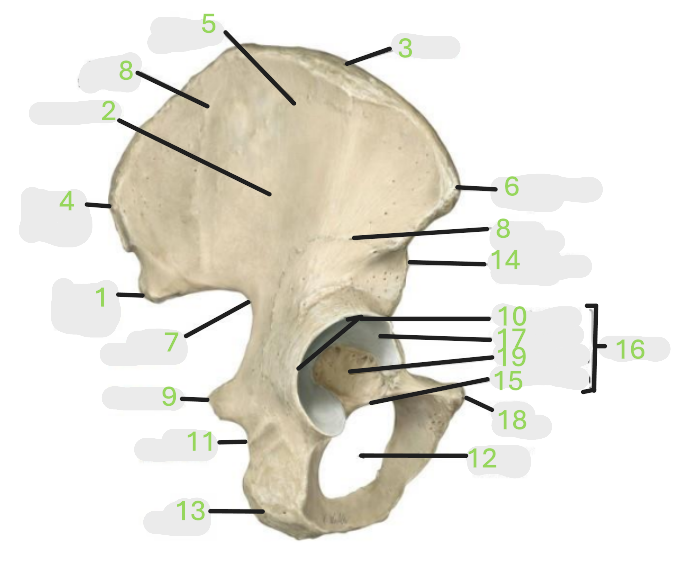

Where is the posterior inferior iliac spine

1

Where is the gluteal surface

2

Where is the iliac crest

3

Where is the posterior superior iliac spine

4

Where is the anterior gluteal line

5

Where is the anterior superior iliac spine

6

Where is the greater sciatic notch

7

Where is the inferior gluteal line

8

Where is the ischial spine

9

Where is the acetabular rim

10

Where is the lesser sciatic notch

11

Where is the obturator foramen

12

Where is the ischial tuberosity

13

Where is the anterior inferior iliac spine

14

Where is the acetabular notch

15

Where is the acetabulum

16

Where is the lunate surface

17

Where is the pubic tubercle

18

Where is the acetabular fossa

19